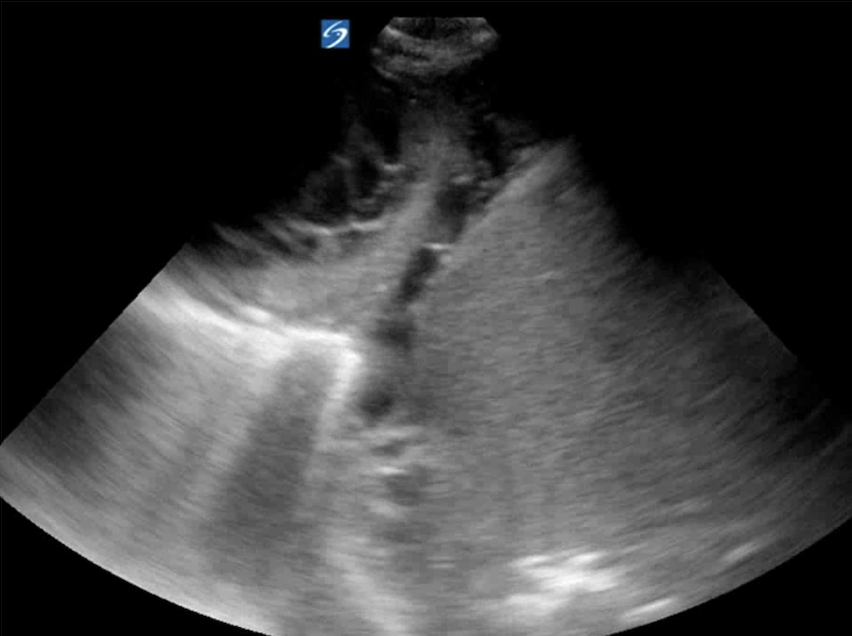

Renal and bladder ultrasound are incorporated within this curriculum to complete the evaluation of AKI and obstructive physiology at the bedside.

Participants develop a question-driven approach to renal POCUS:

• Is obstruction contributing to AKI?

• Is hydronephrosis truly present?

Emphasis is placed on avoiding common pitfalls (e.g., parapelvic cysts mimicking hydronephrosis) and building confidence in technically challenging patients.

• Renal/bladder ultrasound for obstruction, retention, and AKI phenotyping

• Focused renal and bladder ultrasound

• Bedside renal/bladder ultrasound for AKI and urinary retention